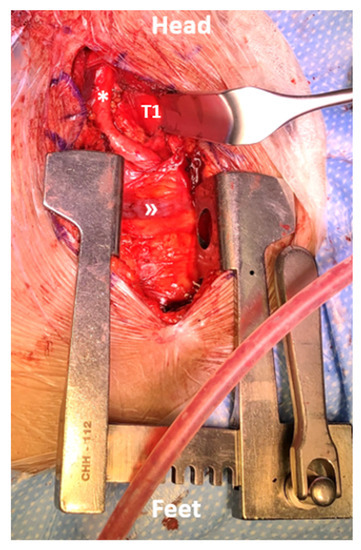

Figure 2.

Intraoperative view of the distraction phase and exposure of the mediastinum for an anterior T1 corpectomy. The proximal carotid artery (*) and brachiocephalic trunk (») are visualized boundaries of the approach.